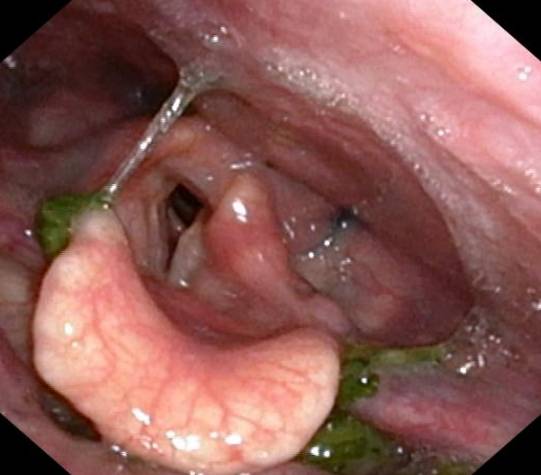

- 纖維內視鏡吞嚥檢查:由耳鼻喉科醫生將將細微的內視鏡經鼻腔進入喉嚨上方,俯瞰患者吞嚥不同質地食物的過程。醫生及治療師能直接觀察喉部組織顏色、殘餘物多寡以及聲帶閉合情況